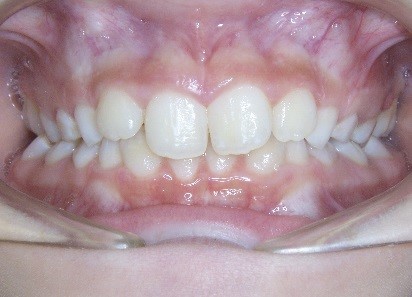

Key #4: When teeth erupt into a prepared site with adequate bone and soft tissue support, it is ideal for long-term stability and sound periodontal support. A similar protocol is followed when preparing a site with a graft for receiving an implant or grafting in an alveolar cleft site to receive the erupting canine. To prepare the space for expansion, follow the same principles for site preparation. In a crowded developing dentition, the plan to develop eruption space will decrease the risk of ectopic eruption with a compromised gingival attachment

Key #2: An expander during the early mixed dentition allows the primary teeth to anchor the expansion appliance. This has significant benefits for permanent dentition that eliminate potential adverse effects, including dehiscence of the buccal bone, gingival recession, and root resorption. Expansion appliances use the strength of the roots and surrounding bone of the teeth to which they are attached. Consequently, those teeth and supporting bone carry the lateral pressure of the expansion as the suture opens. When primary teeth support the expander, the succedaneous bicuspids and canines do not bear any expansion pressure. The newly erupting teeth only benefit from the additional space development the expander has created. The acrylic bonded expander is easily constructed to adapt exclusively to the primary dentition, and has the added benefit of spreading the attachment over several teeth on each side. A banded hyrax appliance can be attached to the second primary molars and canines, or the permanent first and primary first molar. Studies have reported that using a Haas expansion appliance attached to the second primary molars and primary canines is successful and stable.